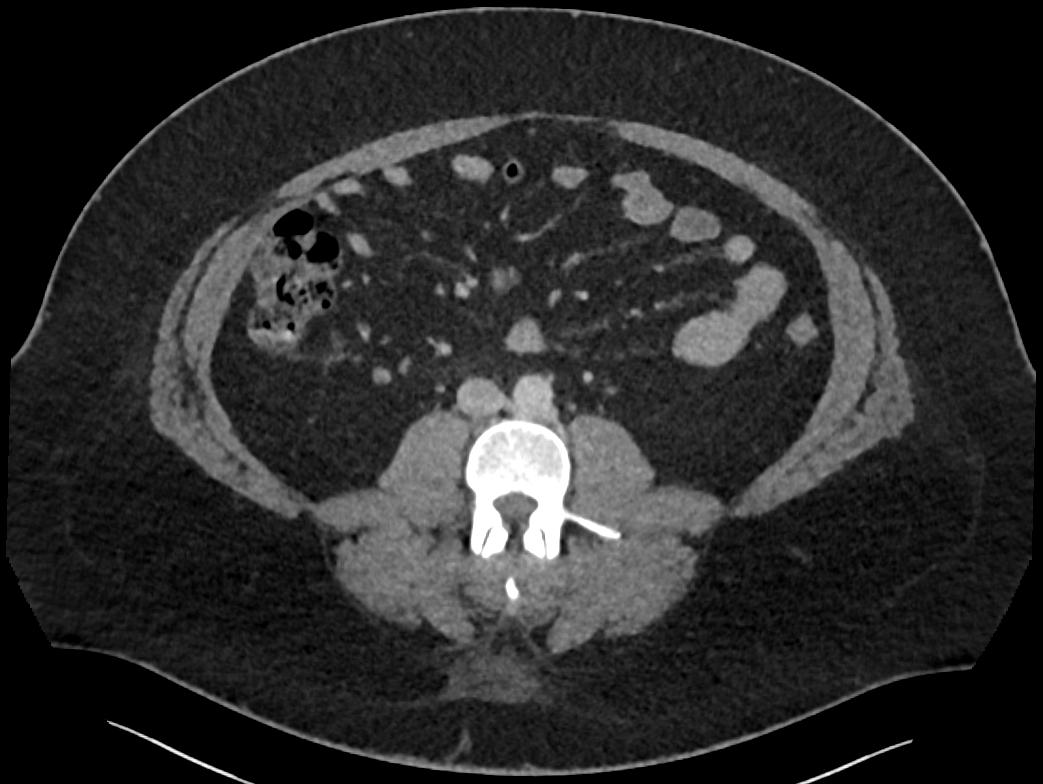

Patient: Padmakumar A. , *1988-04-24, PID: 3000069741773230809

Study Description: CT ABDOMEN

Image Series: Abdomen Ax 3mm [4]

<< Previous | Image 80 of 168 | Next >>